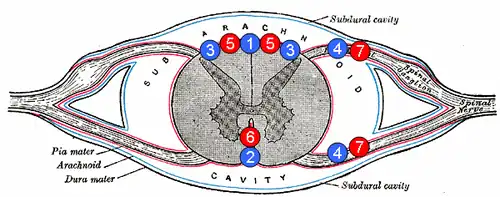

1. задняя спинальная вена

2. передняя спинальная вена

3. заднелатеральная спинальная вена

4. радикулярная (или сегментарная) вена

5. задние спинальные артерии

6. передняя спинальная артерия

7. радикулярная (или сегментарная) артерия

.

Спинальный инсульт

Спинальный инсульт — острое нарушение спинального кровообращения с повреждением спинного мозга и расстройством его функций. Его частота составляет около 1 % от всех инсультов[32]. В зависимости от повреждённых структур спинного мозга, уровня его поражения возникают чувствительные и двигательные расстройства в руках и ногах различной степени выраженности, нарушения функции тазовых органов.